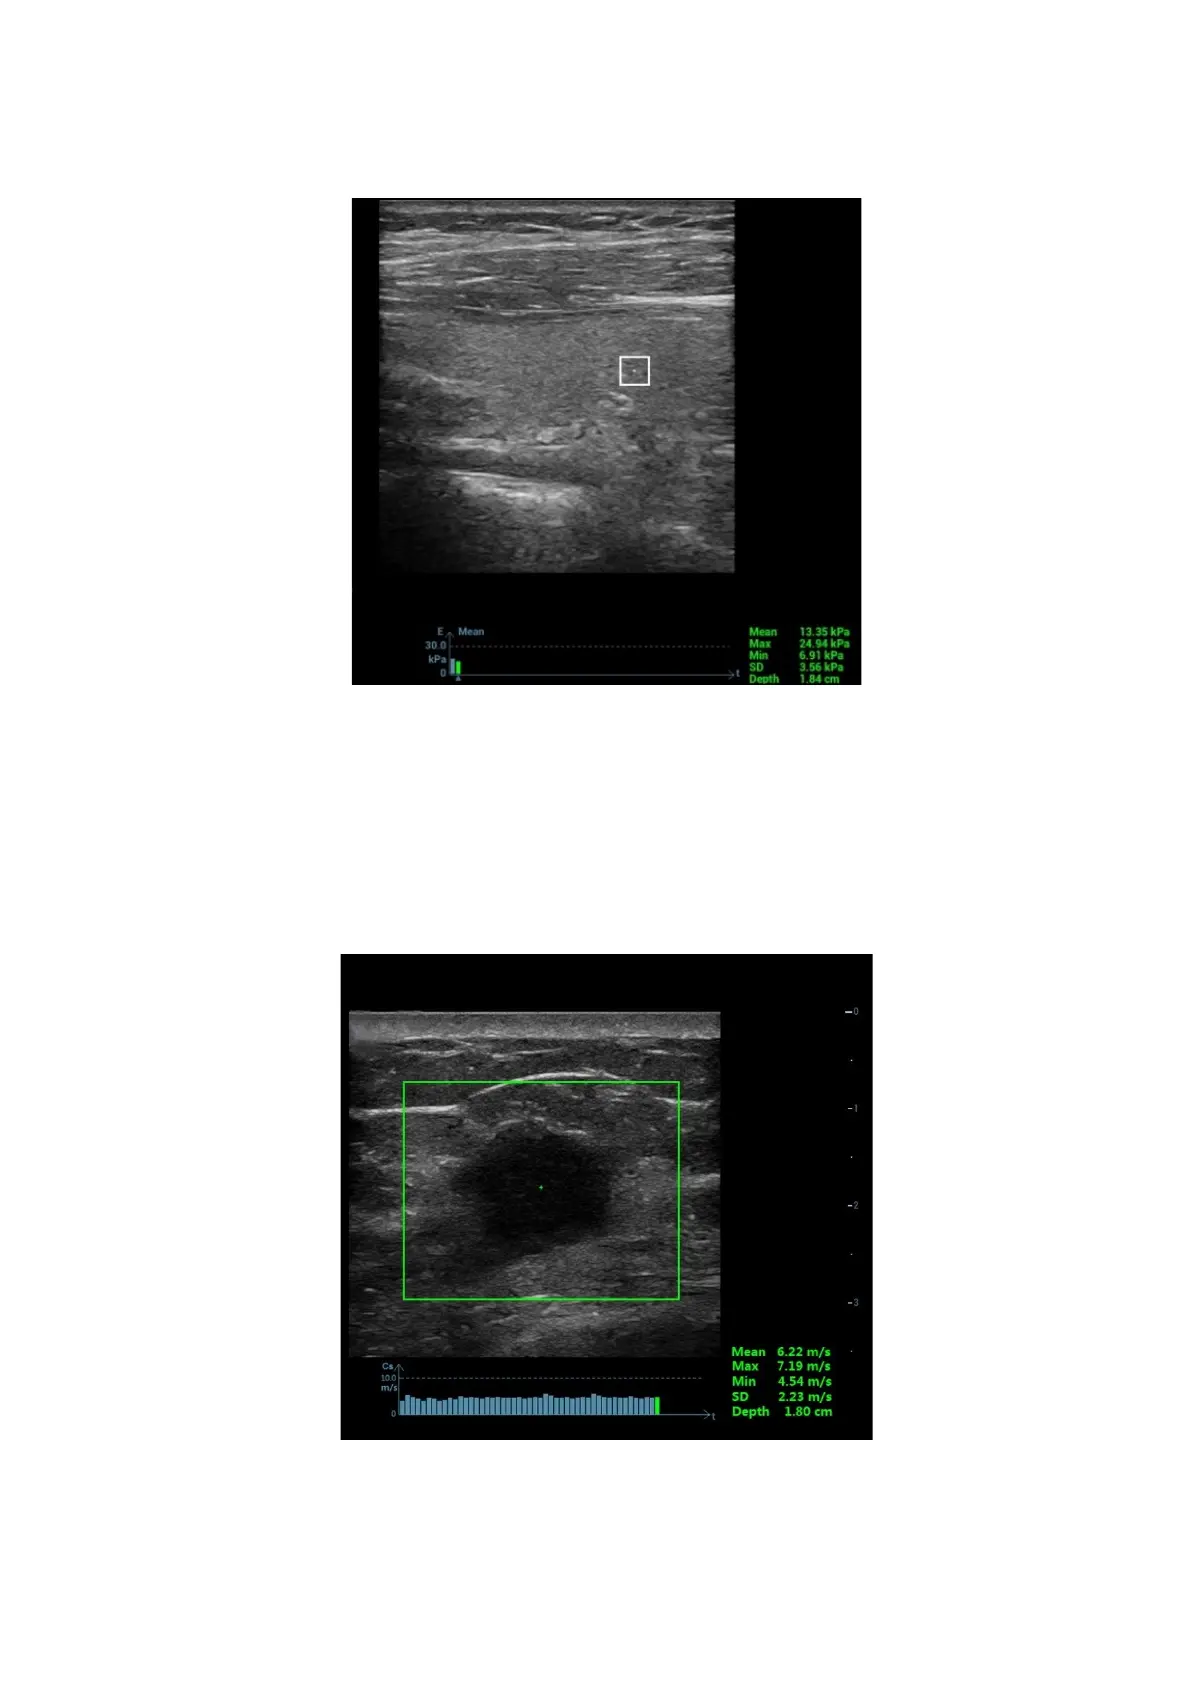

Image Optimization 5-99

2. Tap [Elasto]→[STQ] on the touch screen. Or press the user-defined <STQ> key (set the user-defined

key via [Preset]→[System][iConsole&Footswitch]/[Key Board]) to enter the STQ mode.

3. Adjust the ROI based on the lesion size and the position.

4. Press <Update> to generate the acquisition. Place the probe still with stable force (not pressing,

sweeping or moving the probe) to acquire the image. Adjust the B image parameters to obtain a

premium image.

The stress curve shows at the bottom of the screen after entering the real-time acquisition.

The following indices display besides end of the curve in real-time:

Elasto modulus inside the ROI of the current frame;

The mean value, maximum value, minimum value, SD value of shear velocity;

Depth value of the active elasto modulus.

5. Freeze the image, and replay the image if necessary.

6. Save the single-frame and multi-frame image.

7. Reacquire the image if necessary.